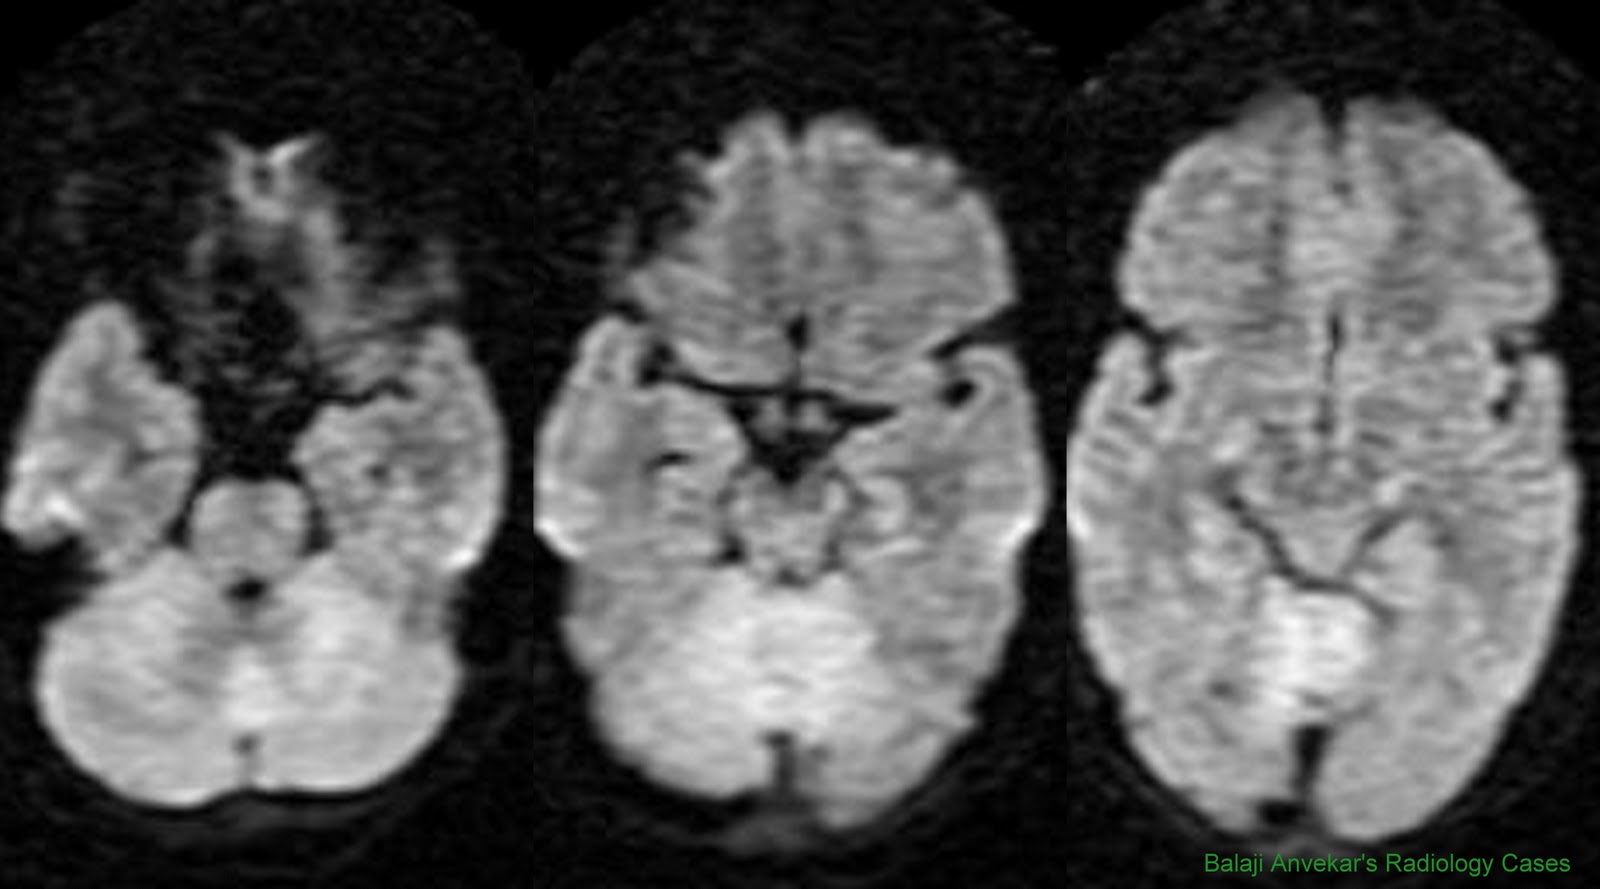

B D A C Figure 1. Diffusion-weighted magnetic resonance images during partial status epilepticus show restricted diffusion in a gyriform pattern in the right ... Get Document